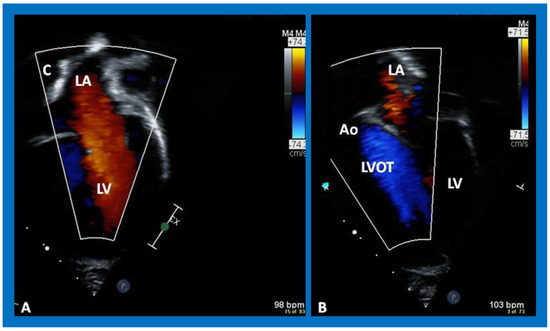

Post-Fontan echocardiographic anatomy is best displayed in apical four chamber views, as demonstrated in Figure 38, Figure 39 and Figure 40. The remnants of the RA and the LA are seen (Figure 38, Figure 39 and Figure 40). The remnants of atrial septum are not usually seen since the atrial septum is completely removed either during bidirectional Glenn or Fontan surgery. Unobstructed pathway allowing emptying of blood flow from the coronary sinus and thebesian veins is usually seen in an apical four chamber view (Figure 40).

The LA is usually normal in size (Figure 38, Figure 39 and Figure 40) and empties into the LV; laminar flow across the mitral valve (Figure 41A) can be seen. Drainage of all four pulmonary veins into the LA may be demonstrated by color flow mapping in multiple echocardiographic views. The LV is either normal in size or slightly dilated. In type I patients with normally related great arteries, the LV outflow into the aorta is demonstrable on echo-Doppler with laminar, unobstructed flow with near normal (~1.0 m/s) Doppler flow velocity (Figure 41B and Figure 42). The RV is small and hypoplastic (Figure 39 and Figure 40). If the VSD has already spontaneously closed (Figure 40), the RV has no communication with any other structures since the connection with the PAs has been severed during bidirectional Glenn or Fontan procedures. If the VSD did not undergo spontaneous closure, the RV forms a cul-de-sac connection with the LV (Figure 39 and Figure 43). In Type I patients with atresia of both tricuspid and pulmonary valves (Type Ia), the hypertrophied RV may protrude into the LV outflow region (Figure 44). However, there is usually no evidence for obstruction across this region (Figure 45).

Figure 41. Selected video frames from an apical views demonstrating laminar flow from the left atrium (LA) to the left ventricle (LV) (A) and from the LV to aorta (Ao) (B). Note laminar flow in the LV outflow tract (LVOT) (B). Medial portion of the conduit (C) is seen in (A).

Applsci 11 09472 g041

Figure 42. Selected video frames from an apical view demonstrating laminar flow from the left ventricle into the aorta (Ao). Note laminar flow in the LV outflow tract (LVOT) and low Doppler flow velocity (~0.8 m/s).

Applsci 11 09472 g042